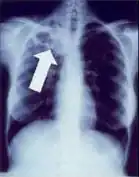

Tuberculosis creates cavities visible in x-rays like this one in the patient's right upper lobe. -

In active pulmonary TB, infiltrates or consolidations and/or cavities are often seen in the upper lungs with or without mediastinal or hilar lymphadenopathy or pleural effusions ( tuberculous pleurisy). However, lesions may appear anywhere in the lungs. In disseminated TB a pattern of many tiny nodules throughout the lung fields is common - the so-called miliary TB. In HIV and other immunosuppressed persons, any abnormality may indicate TB or the chest X-ray may even appear entirely normal.

Abnormalities on chest radiographs may be suggestive of, but are not necessarily diagnostic of, TB. However, chest radiographs may be used to rule out the possibility of pulmonary TB in a person who has a positive reaction to the tuberculin skin test and no symptoms of the disease.

Cavitation or consolidation of the apexes of the upper lobes of the lung or the tree-in-bud sign[7] may be visible on an affected patient's chest X-ray.[1] The tree-in-bud sign may appear on the chest CTs of some patients affected by tuberculosis, but it is not specific to tuberculosis.[7]